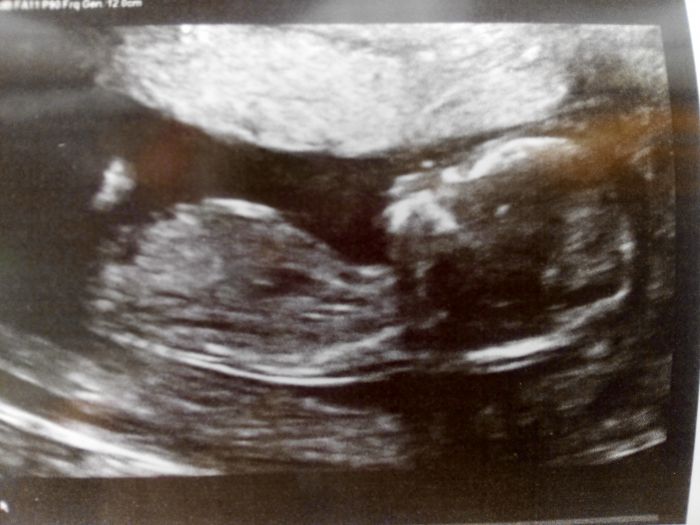

My jsme byli dnes na screeningu a vsechno by melo.byt v poradku,miminko sebou porad pekne mlelo,nelibilo se mu,jak ho pan doktor utlacuje :-) ale vsechno potrebne se zkontrolovalo,ukazal nam obe nozicky,rucicky,spocital vsechny prstiky,miminko si tam prezvykovalo pusinkou,bylo to proste uzasne :-)

[999363] ahoj Leno to je krásná fotecka